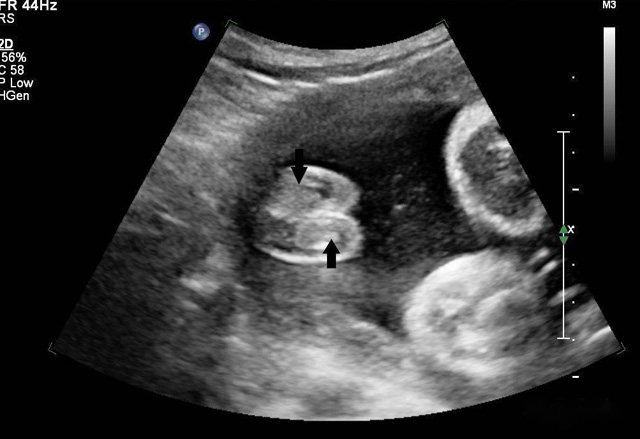

三維超聲技術可用于心臟、腹腔、婦科、產(chǎn)科、小器官、血栓、血管成像等多方面。

超聲造影

超聲波遇見散射體會發(fā)生散射強弱大小,形狀會周圍組織差別、聲阻抗很小散射很微弱,形狀及周圍組織的聲阻抗差別相關。血液內(nèi)盡管含有紅白細胞、血小板,普通超聲設備沒辦法顯示。人為加入不同介質(zhì)在血液中增強散射出現(xiàn)雨霧狀的回聲,這就是超聲造影的基本原理。組織對比超聲利用了這一原理。靜脈注射超聲造影劑隨著血液灌流而發(fā)展或增強器官和組織的成像,為臨床診斷提供成像數(shù)據(jù)基礎。

2.應用

①實質(zhì)性占位性病變;肝臟、腎臟、甲狀腺、乳腺、附件等占位性病變

②右心造影:

③心肌造影:

④輸卵管造影:通過造影劑灌注,顯示輸卵管腔的通暢情況,從而輔助生殖診斷;

⑤超聲介入治療及射頻消融前后評估等。